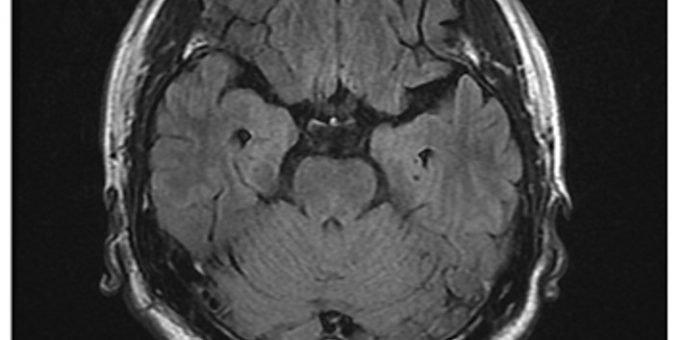

折騰一晚,隔天才接受氧氣治療,並吃了一些藥,雖症狀稍緩解,但仍是相當不舒服,一直到回到台灣,持續的頭暈頭痛才停止。但是因為仍然是間歇性頭痛,所以趕緊到永和耕莘醫院就診。想不到腦部核磁共振(MRI)檢查竟發現在顱內右前額葉有2X3公分大小的血塊(圖四、血塊如白色箭頭裡的黑色腫塊),後來繼續觀察了兩個月,在萬芳醫院追蹤的MRI檢查發現血塊終於消失了,間歇性頭痛才不再發生。

圖四:追蹤的MRI檢查發現血塊終於消失了,間歇性頭痛才不再發生。